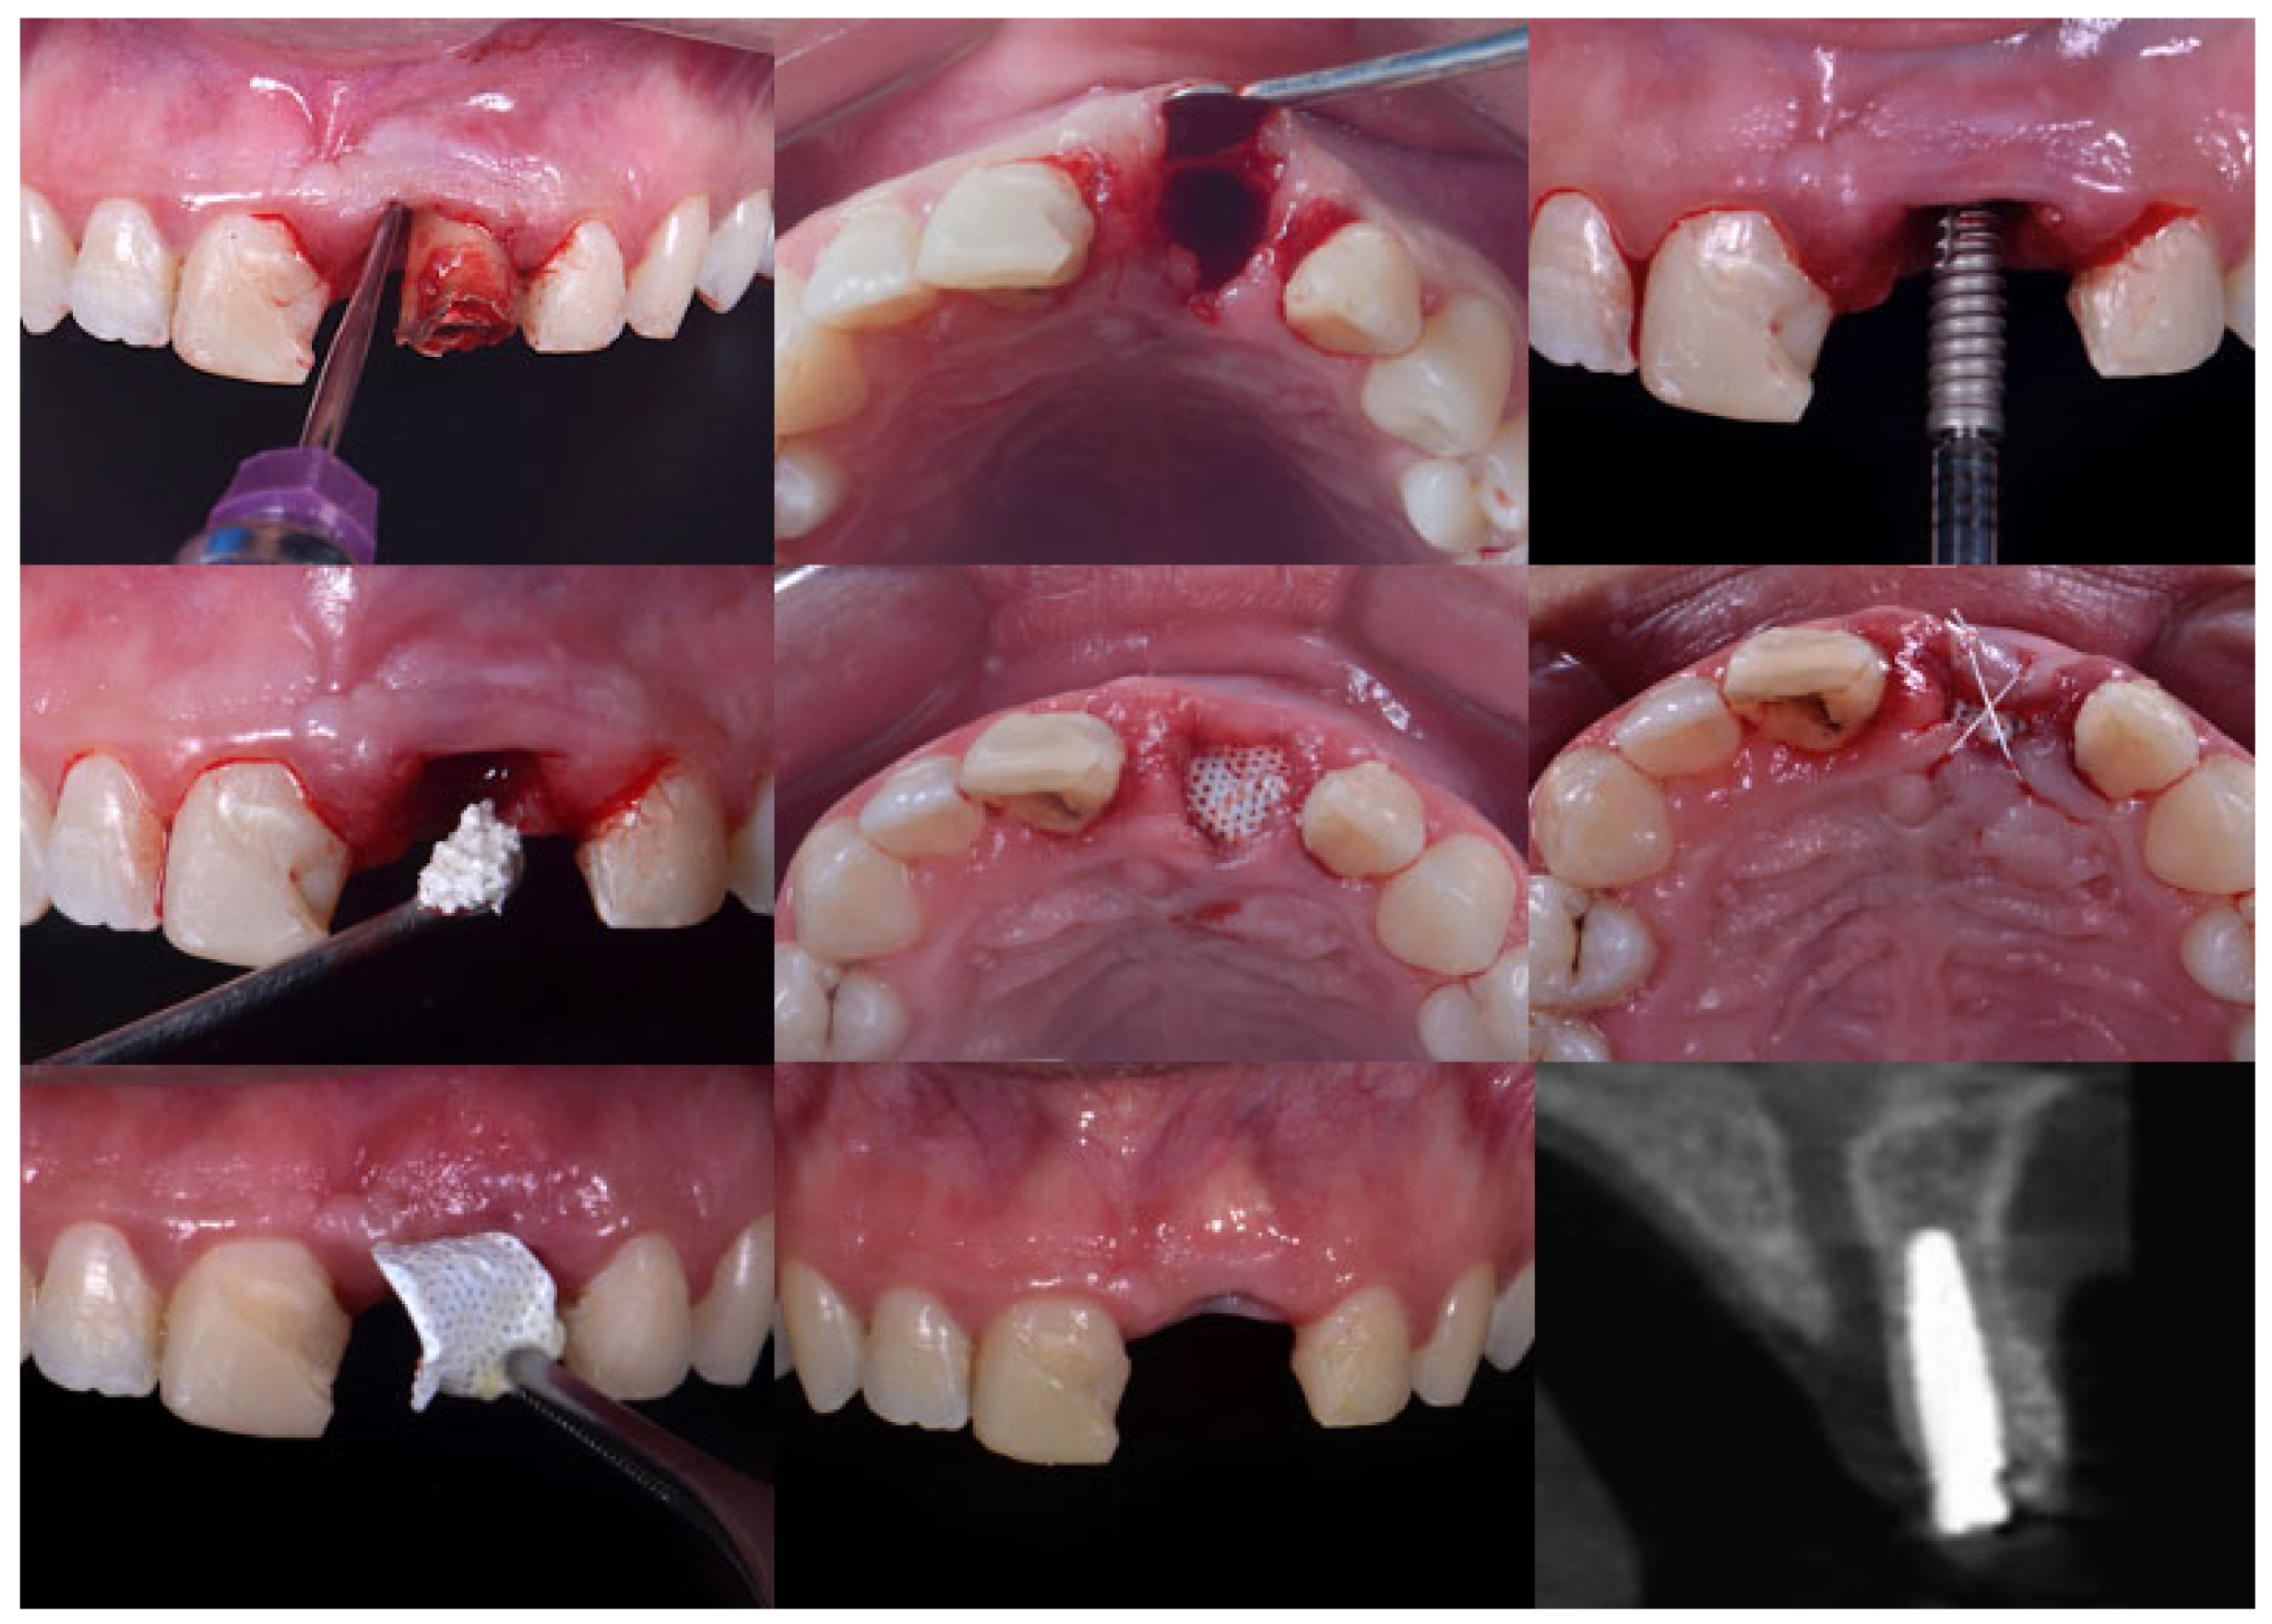

Figure 3.

Clinical view of the surgical procedures: (a) fractured tooth; (b) immediate implant placement with the gaps filled with xenograft material; (c) intentionally exposed d-PTFE suture with Teflon 4.0; (d) occlusal view of the area after 12-month healing period. Note that there was no buccal loss after the procedure.